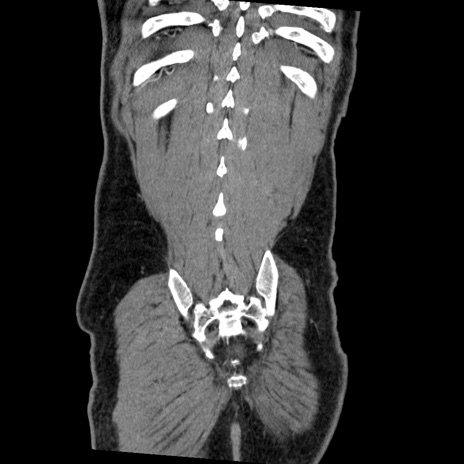

症例22(冠状断像)

【症例】50歳代男性

【主訴】腹痛

【現病歴】AVMからの被殻出血のため回復期リハ病棟入院中。 本日午後3時頃急に下腹部痛が出現した。

【既往歴】AVM、被殻出血、虫垂炎、高血圧

【身体所見】意識晴明、左半身不全麻痺、会話の理解は良好、36.5°C、腹部:膨隆、全体に板状硬、下腹部正中に圧痛点あり、反跳痛-、筋性防御不明、右下腹部にope scar

【データ】WBC 9400、CRP 0.06